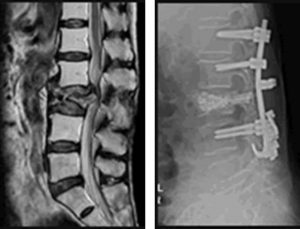

XP MRI

破裂骨折を検査するときには、通常はレントゲンとMRI検査が行われます。

破裂骨折があると、骨の形が保たれていても、MRIを見ると輝度に変化があるので、診断できます。

複数の椎体の骨折がある場合、MRI撮影をすると、陳旧性骨折なのか、新鮮骨折なのかを判断することができます。

交通事故によって脊柱の破裂骨折が起こった場合、ほとんどのケースで緊急手術によって固定されます。